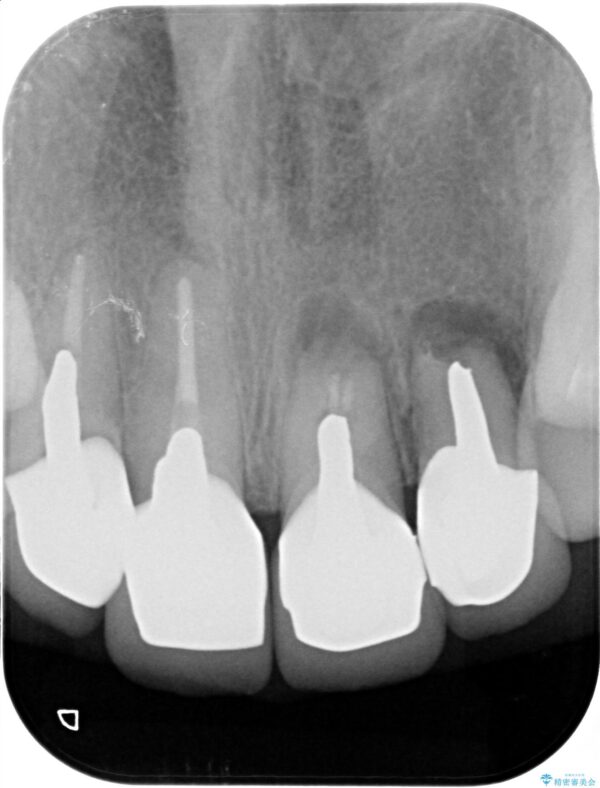

一見して問題ないように見える左側の2前歯は、セラミックを除去してみると亀裂や虫歯の再発が見られました。

抜歯時に可及的に歯肉のボリュームを保つよう骨充填材とコラーゲン製剤による填塞を行い審美的かつ機能的なブリッジとなるよう治療を進めます。

歯槽堤保存術を併用したブリッジ治療 治療前画像 歯槽堤保存術を併用したブリッジ治療 治療前画像 歯槽堤保存術を併用したブリッジ治療 治療前画像 歯槽堤保存術を併用したブリッジ治療 治療前画像 歯槽堤保存術を併用したブリッジ治療 治療前画像 歯槽堤保存術を併用したブリッジ治療 治療前画像 歯槽堤保存術を併用したブリッジ治療 治療前画像 歯槽堤保存術を併用したブリッジ治療 治療前画像 歯槽堤保存術を併用したブリッジ治療 治療前画像 歯槽堤保存術を併用したブリッジ治療 治療前画像